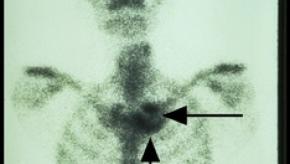

DECT Evidence of Urate Deposition is Associated with X-ray Damage in Gout

Dalbeth and coworkers studied 92 patients with gout and using DECT scanning have shown those with urate deposition on DECT were 8.5-fold more likely to have erosive disease on plain radiographs.